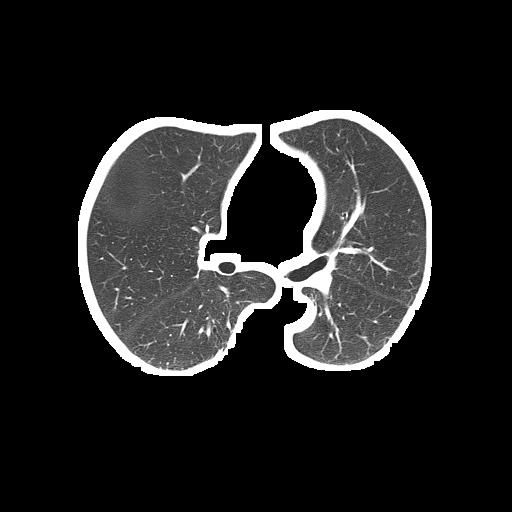

The problem is the segmented lung still contains white borderers like this:

Segmented lung (output):

segmented lung

Unsegmented lung (input):

unsegmented lung